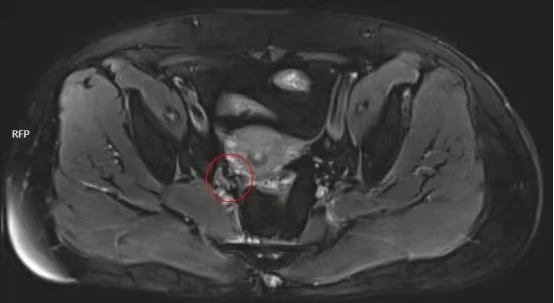

6.治疗效果

经放疗后,宫颈病灶较前部分缩小,宫旁淋巴结消失